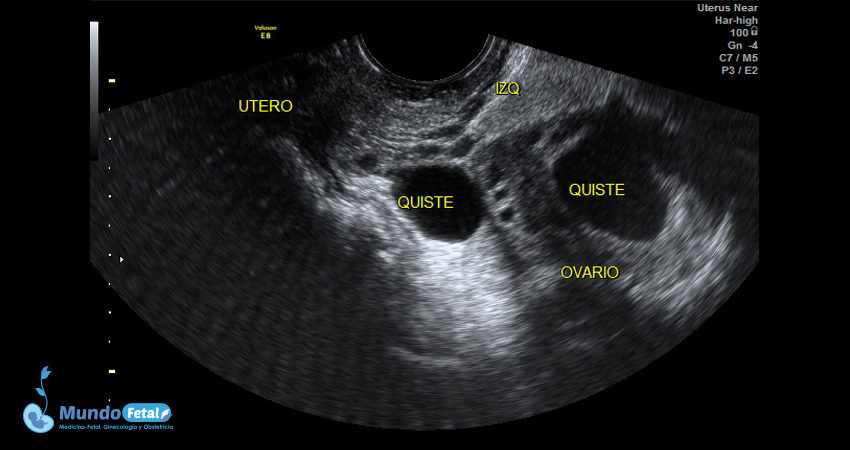

Ultrasonido Pélvico

Estudio anatómico de la región pélvica, que brinda información precisa de (vagina, cérvix, útero, endometrio, trompas de Falopio, ovarios y sus tejidos anexos) de cada uno, descartando alguna complicación de estas estructuras.